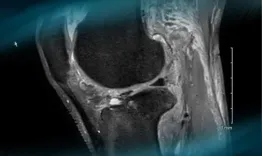

A professional rugby player who underwent ACL reconstruction with fascia lata (Mc FL) a few years ago​, presents with knee torsional trauma. After looking at the X-ray, MRI and pre-op testing, what can you say about this multiligament knee injury? What's the best course of action and how would you approach this case?

Management of a multiligament knee injury in a high-level pivoting sport athlete

Etienne Cavaignac